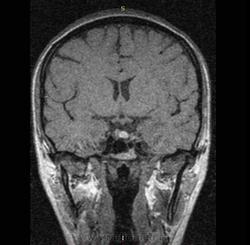

Пациентка девушка 25 лет, направлена для исключения аденомы гипофиза. В течении 6 месяцев отсутствуют менструации. Повышен ФСГ, ЛГ. Родов, травм в анамнезе не было. ВСД по гипотоническому типу, периодические головные боли.

Смущает зона между адено- и нейрогипофизом, которая по Т1, FS практически не видна, а по Т2 имеет предательский пониженный сигнал, и не вписывается в разумное. Может ли это быть отложением гемосидерина (последствие кровоизлияния)? И что может быть субстратом этого измененного сигнала.

Симков не видно, но по описанию похоже на кисту кармана Ратке. Upd Киста видна и на т1 аксиальных. Форма типичная.

Она, ККР.